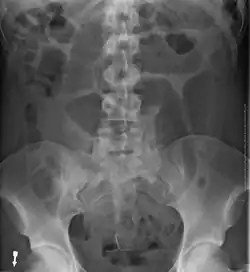

- Abdominal x-ray – tire-like shadow arising from the right iliac fossa and passing to the left

Plain X ray of a cecal volvulus -